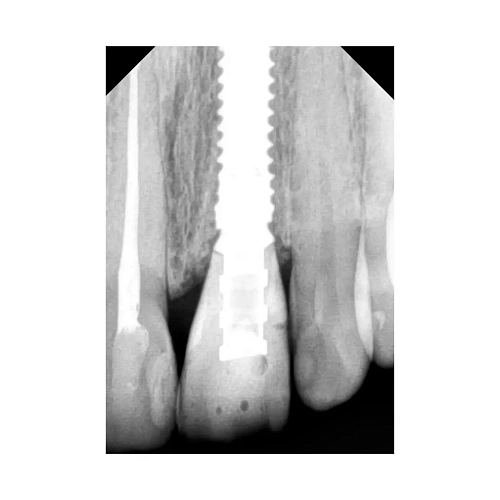

На фото пациенту проведена одномоментная имплантация